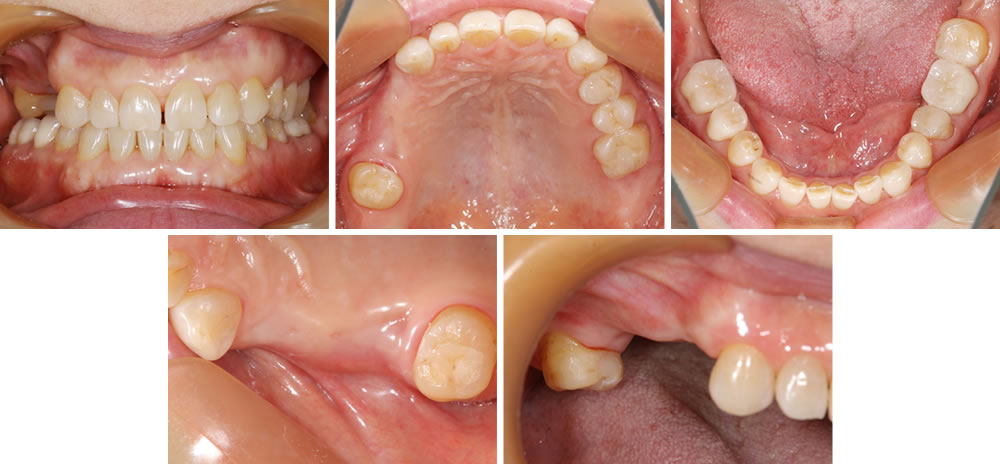

セラミック治療後および右上欠損部治癒後

抜歯を行なって6ヵ月経過した状態です。

入れ歯を作成するにあたって、歯を抜いた直後はまだ歯茎や骨の治癒が行われていないため、適合の良い入れ歯を作る事ができません。抜歯をした後の歯茎はボリュームが減少して形が変化していきます。

目安としては3ヵ月目までが大幅に変化し、6ヵ月目ぐらいまで微妙に変化していきます。しっかりと歯茎や骨の変化が落ち着いたタイミングで入れ歯を作成する事が適合の良い入れ歯を作成するためのポイントです。